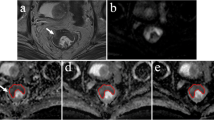

This study explored models of monoexponential diffusion-weighted imaging (DWI), diffusion kurtosis imaging (DKI), stretched exponential (SEM), fractional-order calculus (FROC), and continuous-time random-walk (CTRW) as diagnostic tools for assessing pathological prognostic factors in patients with resectable rectal cancer (RRC).

RRC patients who underwent radical surgery were included. The apparent diffusion coefficient (ADC), the mean kurtosis (MK) and mean diffusion (MD) from the DKI model, the distributed diffusion coefficient (DDC) and α from the SEM model, D, β and u from the FROC model, and D, α and β from the CTRW model were assessed.

There were a total of 181 patients. The area under the receiver operating characteristic (ROC) curve (AUC) of CTRW-α for predicting histology type was significantly higher than that of FROC-u (0.780 vs. 0.671, p = 0.043). The AUC of CTRW-α for predicting pT stage was significantly higher than that of FROC-u and ADC (0.786 vs.0.683, p = 0.043; 0.786 vs. 0.682, p = 0.030), the difference in predictive efficacy of FROC-u between ADC and MK was not statistically significant [0.683 vs. 0.682, p = 0.981; 0.683 vs. 0.703, p = 0.720]; the difference between the predictive efficacy of MK and ADC was not statistically significant (p = 0.696). The AUC of CTRW (α + β) (0.781) was significantly higher than that of FROC-u (0.781 vs. 0.625, p = 0.003) in predicting pN stage but not significantly different from that of MK (p = 0.108).

The CTRW and DKI models may serve as imaging biomarkers to predict pathological prognostic factors in RRC patients before surgery.